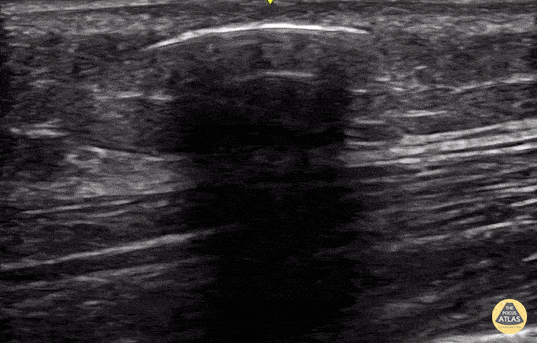

11 year old came in with bleeding and pain in the leg after jumping on the bed. On exam there was a small 5 mm skin defect in the left lateral lower leg. POCUS was performed with a high frequency transducer in long axis adjacent to the skin defect. Identified was normal appearing heterogenous subcutaneous tissue anterior to normal appearing striated muscle. Both were partially obscured by a smooth, semi-rounded hyperechoic arc with dense posterior shadowing and reverberation artifact, located just deep to the dermis, concerning for a dense foreign object. The existing skin defect was widened slightly, and a shard of glass was removed. Contributor: Allie Grither, MD, St. Louis Children's Hospital (Washington University in St. Louis), @AGPemMD